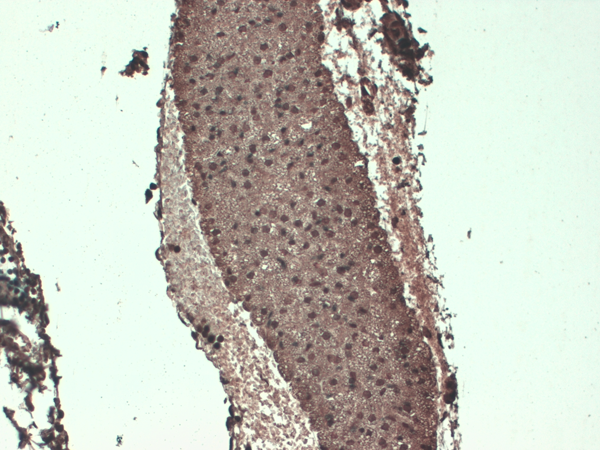

IHC (Immunohistochemisry)

(Immunohistochemistry analysis using Mouse Anti-Sodium Iodide Symporter Monoclonal Antibody, Clone 14F. Tissue: Trachea. Species: Mouse. Fixation: 10% Formalin Solution for 12-24 hours at RT. Primary Antibody: Mouse Anti-Sodium Iodide Symporter Monoclonal Antibody at 1:1000 for 1 hour at RT. Secondary Antibody: HRP/DAB Detection System: Biotinylated Goat Anti-Mouse, Streptavidin Peroxidase, DAB Chromogen (brown) for 30 minutes at RT. Counterstain: Mayer Hematoxylin (purple/blue) nuclear stain at 250-500 ul for 5 minutes at RT.)